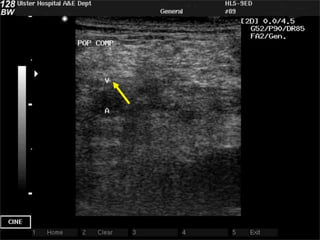

4: popliteal fossa

!   Lie patient on side, or lift leg

!   Popliteal vein

! Superficial to popliteal artery

! visualise bone beneath

! follow it to the trifurcation